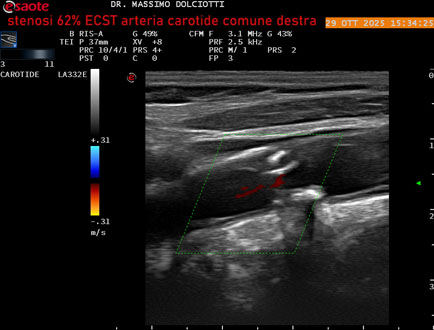

Data inserimento: 30/10/2025

Ecografia del: 29/10/2025

Strumento: Esaote MyLab Eight

Sonda: Lineare Multifrequenza 3-11 MHz

Età Paziente: F 75 anni

Motivazione dell'esame: controllo in pz con ateromasia carotidea ed ipercolesterolemia.

Commento all'esame: le immagini ed il video documentano all'arteria carotide comune destra placca disomogenea tipo 3 della classificazione di Gray Weale, che determina stenosi del 62% calcolato con metodo ECST.

Conclusioni: stenosi del 62% ECST dell'arteria carotide comune destra (62% ECST stenosis of the right common carotid artery).

Presentazione: Dr. Massimo Dolciotti - Ancona

Elaborazione digitale: Andrea Dini - Ancona